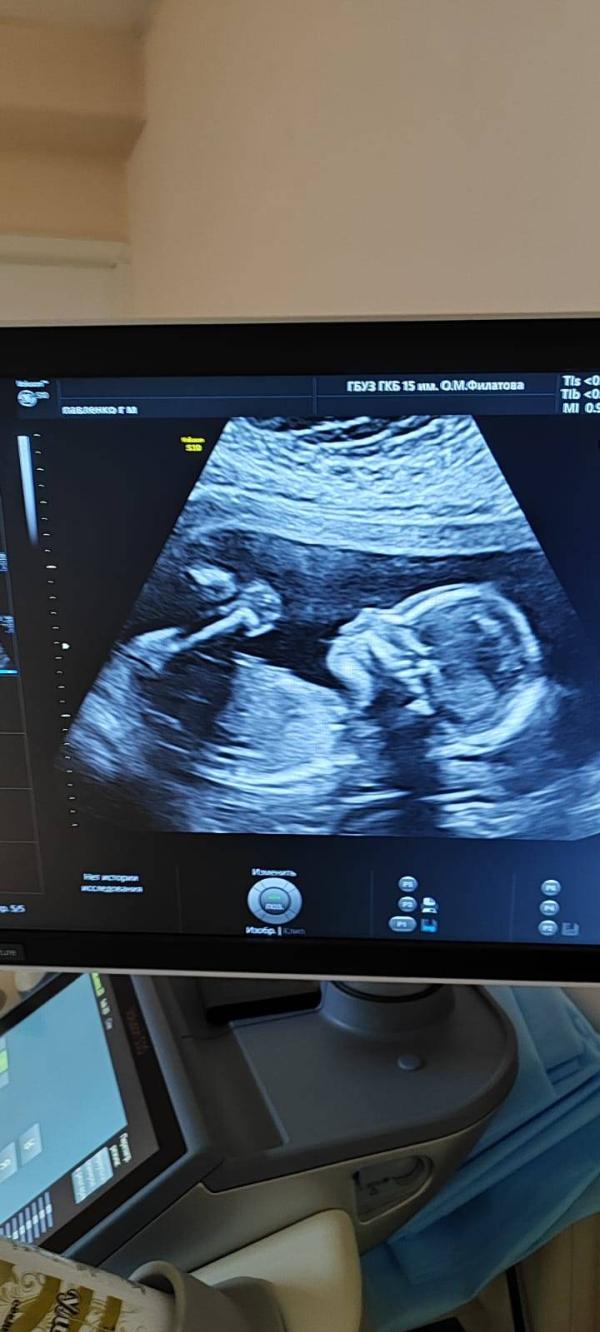

2 скрининг, 311 гр, мы ждём нашу горошинку❤

Сегодня, по месячным 19,4 по 1 скринингу 19,1